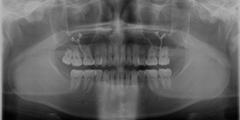

| 診断名 | 上下顎前突 |

| 使用装置 | 上下顎マルチブラケット矯正装置 上顎左右大臼歯部骨接合用プレート |

| 抜歯or非抜歯 | 抜歯 |

| 抜歯部位 | 上顎右側:第二小臼歯 上顎左側:第二小臼歯 (第三大臼歯) 下顎右側:第一小臼歯 (第三大臼歯) 下顎左側:第一小臼歯 (第三大臼歯) |